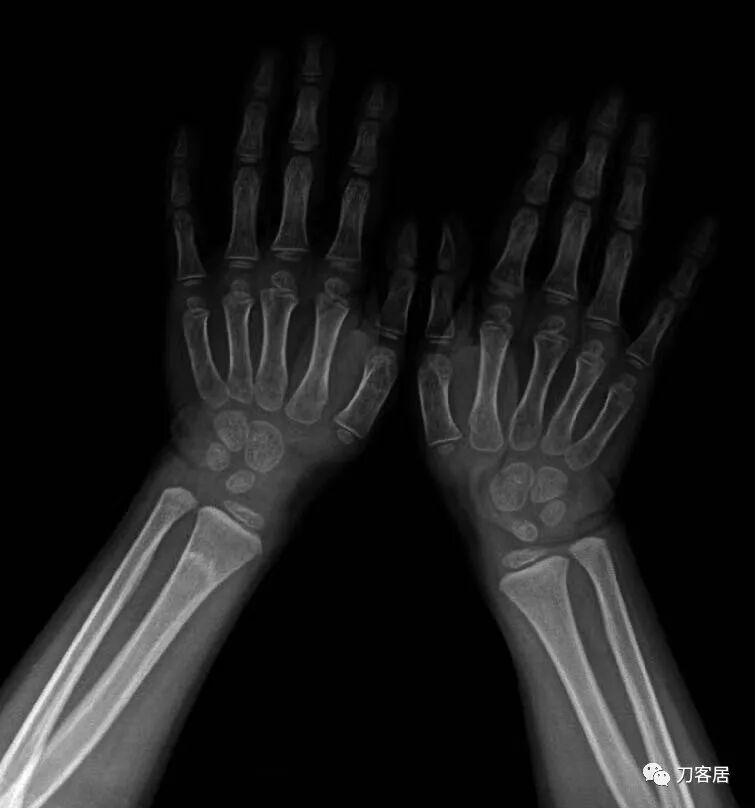

戴功夫医生7月26日晚上提供两例使用中医小夹板治疗的尺桡骨双骨折病例

病例1. 患儿男, 6岁 前图1-4片子是伤后1小时,图5-6是伤后半个月,图7-8是伤后5个月。

图1. 伤后1小时手法复位前。

图2. 伤后1小时手法复位前。

图3. 伤后1小时手法复位小夹板外固定后。

图4. 伤后1小时,小夹板外固定后。

图5. 伤后半个月复查。

图6. 伤后半个月复查。

图7. 伤后5个月复查。

图8. 伤后5个月复查。